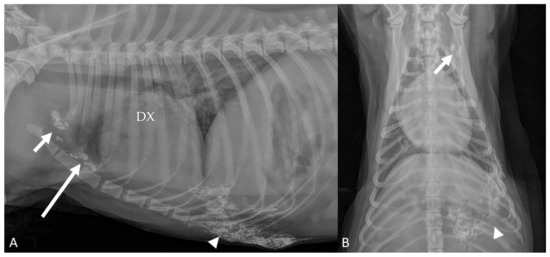

3.2. Lymph Node Drainage